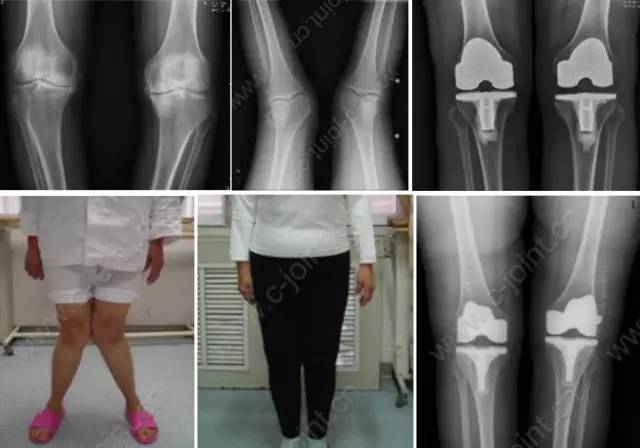

各种晚期骨关节病的关节置换手术治疗是北京清华长庚医院关节外科中心的一大特色,包括股骨头坏死、髋膝骨关节炎、类风湿关节炎、强直性脊柱炎、髋关节发育不良、关节强直、超过80岁的超高龄股骨颈骨折患者的关节置换手术等,我中心在人工关节初次置换及翻修上作了大量工作,置换的难度和手术效果方面已达到国际先进水平,导航下全膝关节置换术:大大提高膝关节置换手术的精确度。

局限性关节置换手术(UKA)

全膝关节表面置换手术(TKA)

成人肢体骨与软组织畸形、如:斜颈畸形、臀肌筋膜挛缩症、先天性骨关节疾病畸形、先天性髋关节脱位分期治疗、先天性马蹄内翻足矫形术、X型腿、O型腿、创伤后畸形、小儿麻痹后遗症的肢体畸形矫形、脑性瘫后遗症的肢体畸形矫形等。

胫骨截骨矫形手术(HTO)

股骨远端截骨矫正膝外翻